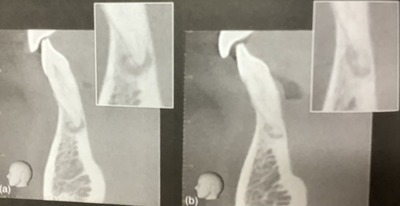

CBCTを取りました。

普通のレントゲンから診断がつかない根っ子の影なんで。

CTでは黒くなっている部分と逆に白く見える所もあった。

下の前歯のセメント質骨異形成症です。

歯の神経の病気ではありません。

似てるけど。